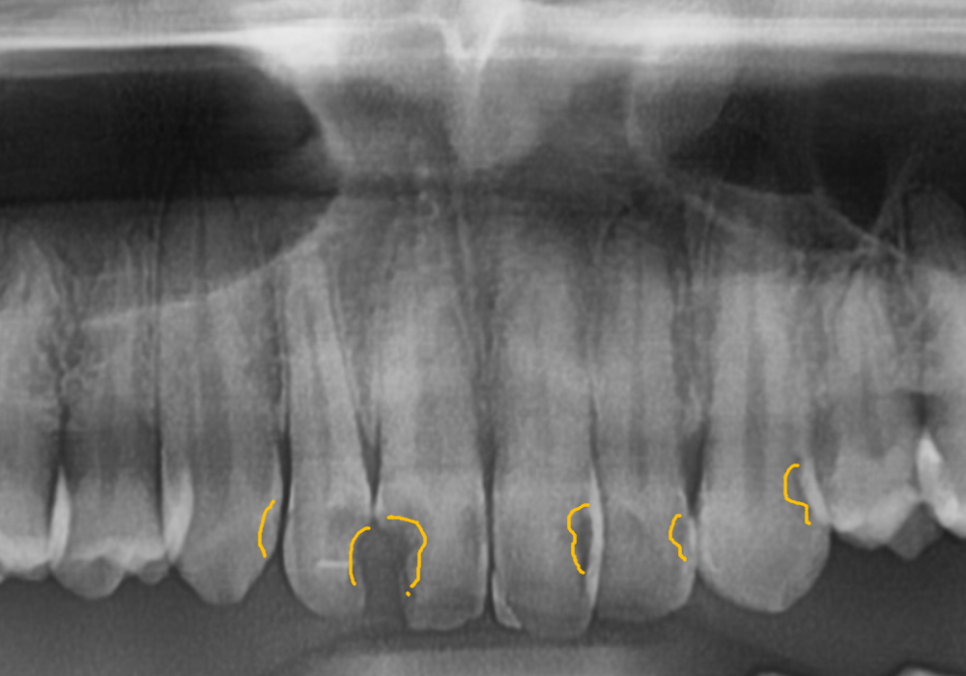

그 뿐만 아니라, 뿌리 끝에 까~맣게

염증이 비춰보이네요

빨간색으로 표시한 부분이

주요 신경인 '하치조 신경'인데,

거의 맞닿아 있을 정도로

염증이 많이 퍼져있는 게 보이시나요?

안타깝지만, #46 치아는

서둘러 발치를 진행해야 했습니다.

여기에 더해 바로 뒤쪽 어금니(#47)의

옆면까지 충치가 전이되어 함께 썩고 있었는데요.